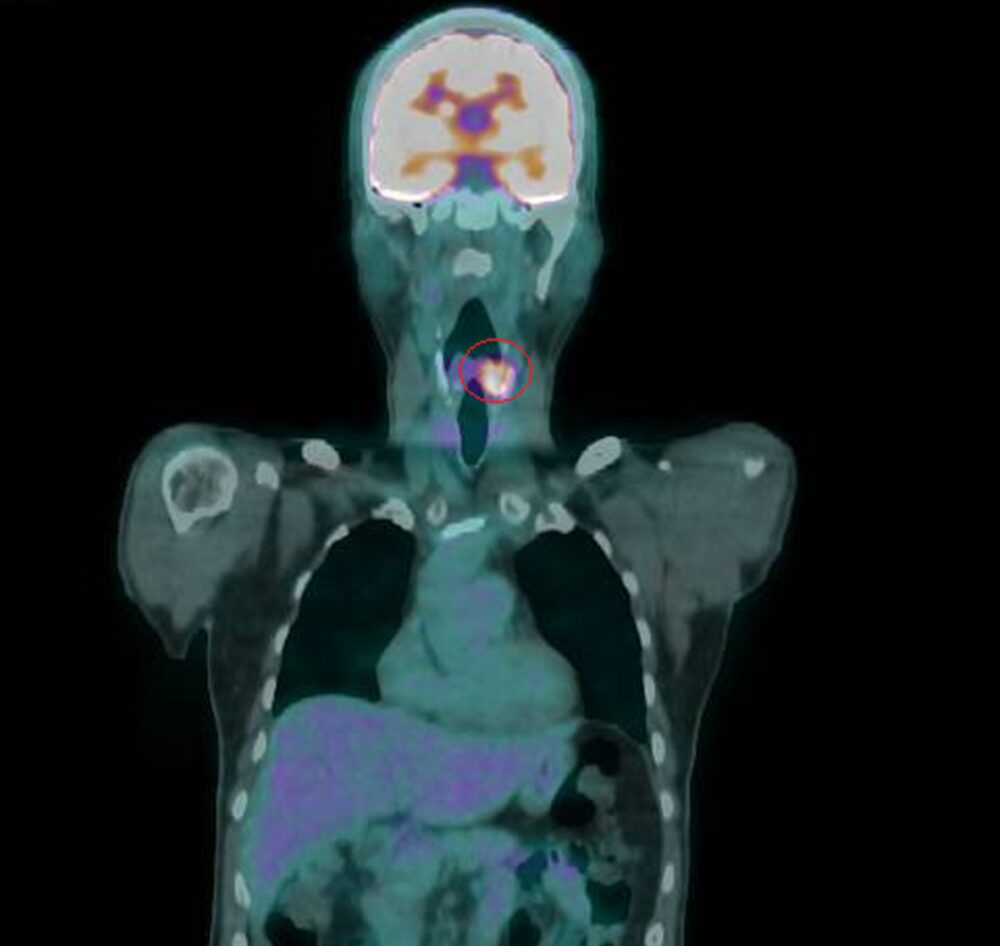

▲電腦斷層等檢查發現,其左下咽處有個2公分的腫瘤。(圖/彰化醫院提供)

衛福部彰化醫院耳鼻喉科主任許嘉方表示,曾先生3年前喉嚨疼痛不癒,經內視鏡、電腦斷層等檢查發現,其左下咽處有個2公分的腫瘤,切片確定為惡性,是第2期癌症,不進行切除手術,採放射及化學療法,治療後腫瘤消失。